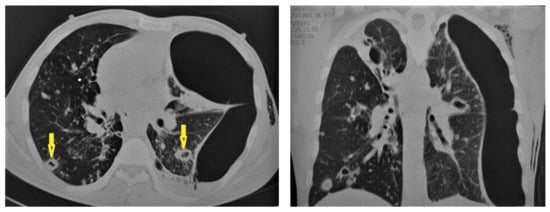

Figure 10. Reactivation of TB in an adult man with chronic cough. Selected axial images of lung CT show cystic bronchiectasis, due to old infection, with peribronchial thickening and air fluid level involving both lower lobes. Scattered tree in bud pattern and infected cystic bronchiectasis indicate active TB.

Even after full treatment of pulmonary TB, complications and residual changes may affect quality of life; these complications can be misinterpreted as other active diseases, causing diagnostic pitfalls. TB complications in the lung parenchyma include tuberculoma, thin-walled cavities, cicatrisation collapse (Figure 9), and lung cancer, although this is rare. Complications in the airway include bronchiectasis (Figure 10) and tracheobronchial stenosis. Extrapulmonary complications include pleural thickening and calcification, fibrothorax, bronchopleural fistula, and pneumothorax (Figure 11). Vascular complications include Rasmussen aneurysm, calcified mediastinal lymph nodes, fibrosing mediastinitis, and constrictive pericarditis [23].